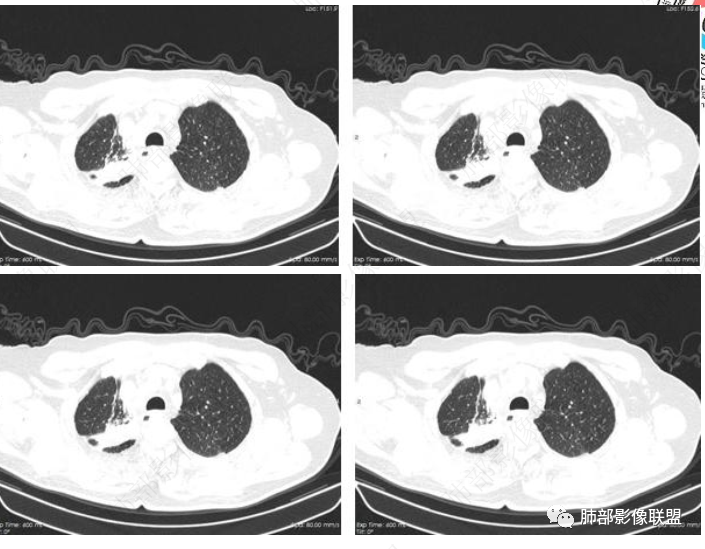

主要在慢性炎性病变与腺癌之间鉴别,病灶有膨胀性生长,支气管未见阻塞,支气管僵硬,增强病灶内可见强化,支气管内部壁增厚,偏向占位性病变,腺癌可能。

右肺上叶可见一团块影,边界清,有膨隆有凹陷,边缘可见毛刺,斜裂可见牵拉,不均匀强化,内可见液化,临近支气管未见明确阻塞,考虑腺癌可能,鉴别脓肿,结核等

病史2年。右肺上叶团片影,边缘部分清晰,平直,相邻纵隔侧胸膜黏连较广泛,周围见斑点。增强均匀强化。首选炎性肉芽肿性病变(慢性炎症,结核)。肿瘤性病变待排。食道上段形态异常建议相关检查。

右肺上叶团块,边缘毛糙,长索条,周围斑点影,邻近胸膜增厚,不均匀强化,其内小低密度灶边界清,考虑炎性肉芽肿,腺癌待排

老年男性,咳嗽2年,右上肺类圆形新生物,毛刺,不均匀强化,考虑肺癌,支气管截断不明显,腺癌?

右上胸廓缩小,叶间裂移位,尖段软组织影,前段支气管壁增厚,双上肺多发结节及条片影,增强后尖段软组织影内见多发低密度影,呈环状强化,考虑慢性肉芽肿,腺癌待排

男性,69岁 反复咳嗽2年余,加重3天入院。CT示右肺上叶尖段不规则实变影,周边伴条索影,支气管未见明显堵塞,增强不均匀强化,考虑为恶性,腺癌可能

老年男性,慢性病程,右肺上叶团块影,边界清晰,边缘毛刺,脐凹征,胸膜牵拉,不均匀强化,支气管壁增厚,考虑恶性,腺癌可能,鉴别肉芽肿、结核

男,69,反复咳嗽2年,加重3天入院,右肺上叶软组织密度肿块影,边界尚清晰,边缘见毛刺及胸膜牵拉,右肺上叶支气管壁增厚,增强扫描不均匀性强化,考虑腺癌可能,鉴别炎性病变。

老年男性,右肺上叶体积小,见高密度团块,边缘模糊,并见多发长索条,增强后不均匀强化,考虑炎性肉芽肿性病变,鉴别腺癌

病程长,右肺上叶团片影,边缘毛糙,部分膨隆,长索条,周围长条索及结节,邻近胸膜增厚,不均匀强化,首先考虑炎性肉芽肿,鉴别腺癌

右肺上叶团块周围多发斑索,不均匀强化,支气管无明显堵塞,咳嗽两年,首先考虑慢性炎性病变,肺结核可能,鉴别腺癌

膨隆,上叶体积缩小,可见强化,相应胸膜肥厚,感觉支气管通,纵隔未见明显肿大淋巴结,考虑慢性肉芽肿,鉴别腺癌,结核

右肺上叶见不规则团块,边缘清晰,周围可见长索条及斑片影,胸膜顶增厚,右侧斜裂部分增厚,右上肺体积略缩小,增强后不均匀强化,考虑炎性肉芽肿性病变,结核?鉴别腺癌

右肺上叶体积变小,见不规则实性病灶,边缘有平直,长软毛刺,邻近胸膜明显增厚,叶间胸膜牵拉上提、局部凹陷;病灶周围不干净,可见长索条影;近端支气管壁略增厚。增强后增强不均匀,有低密度坏死,间隔较厚。考虑慢性炎性肉芽肿,结核可能,鉴别腺癌。

右侧胸廓变小,右肺上叶团块,边缘毛糙,长索条,周围斑点影,邻近胸膜增厚,气管不规整,密度不均,不均匀强化,考虑炎性肉芽肿,腺癌待排。

右肺上叶尖后段不规则斑块病灶,后缘以斜裂为界,有边缘平直,周围见纤维及多发小卫星灶,邻近胸膜反应性增厚,纵隔胸膜下少量积液,同时右肺中叶内侧段支气管扭曲及牵引性扩张,周边见爬行征,胸廊入口变窄,纵隔未见淋巴结肿大,综合上述慢性炎性肉芽肿,结核可能性大,支气管镜肺泡灌洗!